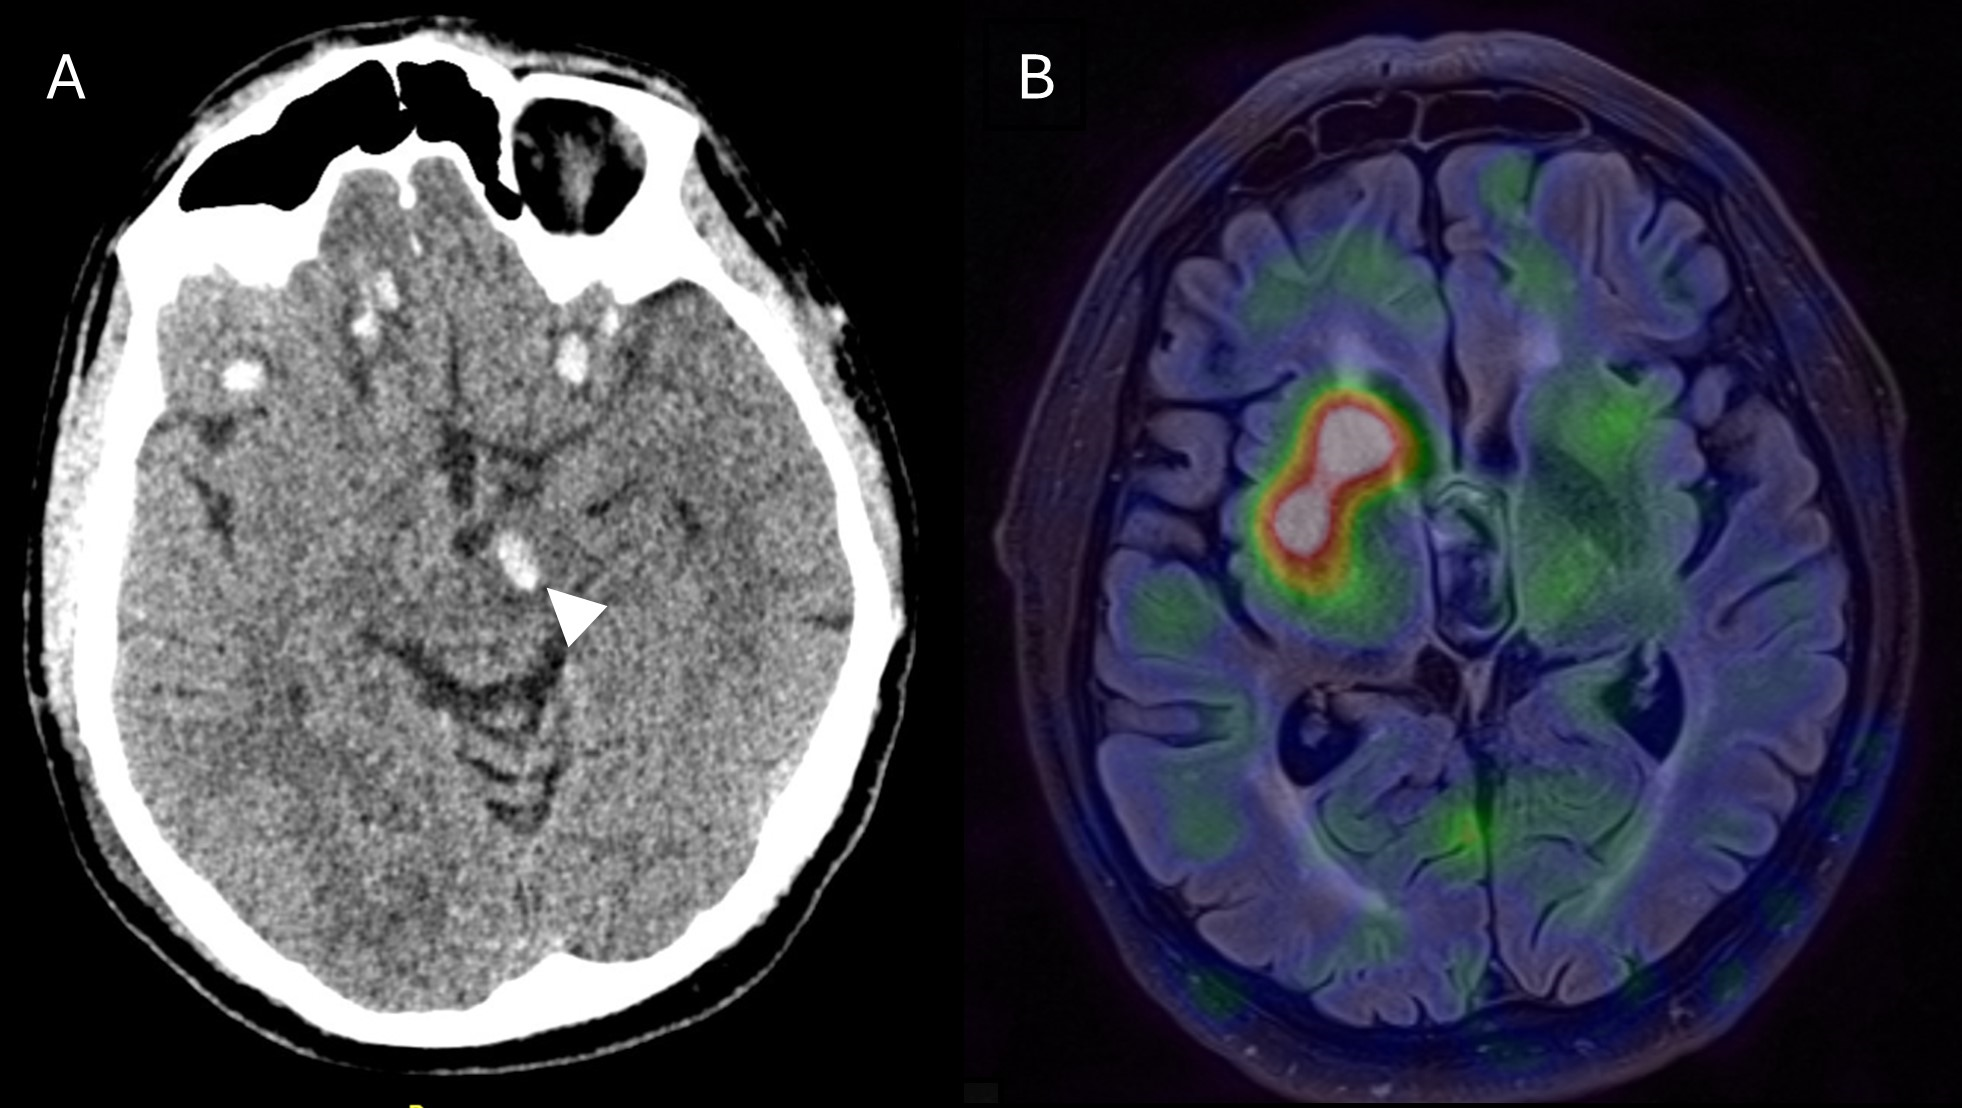

Če pa vaskularne spremembe, kot so lakunarne ishemične možganske kapi, prizadenejo striatum, črno substanco ali nigrostriatne povezave, je lahko izvid patološki. Kljub temu nam lahko tak izvid pomaga pri diagnozi, saj je razporeditev izpada kopičenja radiofarmaka drugačna kot pri PB. Pri vaskularnem parkinsonizmu ne pričakujemo kavdorostralne okvare striatuma, temveč izpad kopičenja radiofarmaka v omejenem predelu bazalnih ganglijev, z ohranjenim kopičenjem v posteriornem putamnu 15. Tovrsten izvid je še posebej pomemben, saj raziskave kažejo, da imajo bolniki z vaskularnim parkinsonizmom in nigrostriatno okvaro boljši odziv na dopaminergično terapijo kot tisti z normalno scintigrafijo dopaminskega prenašalca 15.

Nedavno smo obravnavali 56-letnega moškega, ki je utrpel difuzno aksonsko možgansko poškodbo s številnimi hemoragičnimi lezijami, vključno z lezijo v področju leve črne substance (Slika 3A) 16. Kljub uspešni rehabilitaciji so vztrajale številne težave, vključno z desnostranskim parkinsonizmom. Scintigrafija dopaminskega prenašalca je razkrila hudo izgubo nigrostriatnih dopaminergičnih povezav na levi strani (Slika 3B). Kopičenje radiofarmaka je bilo v levem striatumu popolnoma odsotno, v nasprotju s PB, kjer tudi v napredovali bolezni pričakujemo ostanek kopičenja v kavdatnih jedrih. Kljub odsotnosti nevrodegenerativnega vzroka je uvedba dopaminergične terapije občutno izboljšala simptome.